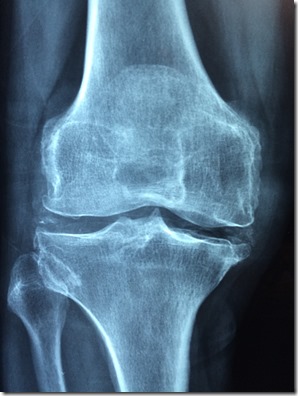

El diagnóstico de una meniscopatía es clave para tratarlo. Se confirma mediante un examen físico detallado y una resonancia magnética. Una vez identificada la lesión, la intervención quirúrgica puede ser necesaria, especialmente si el dolor y las limitaciones funcionales persisten.

Actualmente, la cirugía de menisco se realiza mayoritariamente con técnicas artroscópicas. Este procedimiento mínimamente invasivo permite reparar o extirpar el tejido dañado a través de pequeñas incisiones. “La artroscopia reduce significativamente los riesgos asociados a las cirugías tradicionales y permite una recuperación más rápida. En la mayoría de los casos, el paciente puede apoyar la pierna operada de inmediato y retomar sus actividades cotidianas en pocos días”, explica Fernando Bascuñán, traumatólogo de Clínica Miguel Claro.